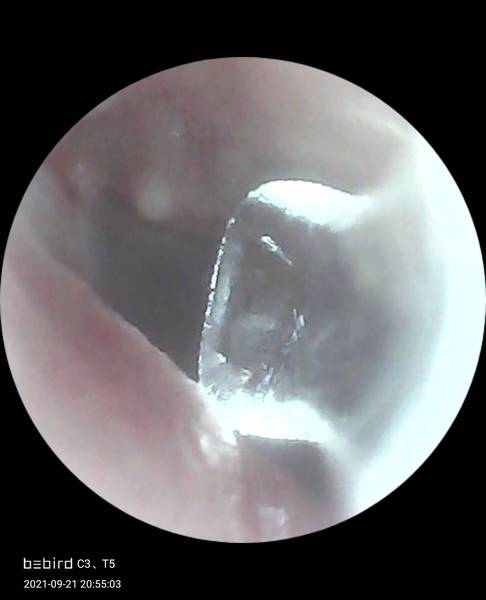

So I have a fab gadget that let's me see isnde my ears and remove wax.. Tonight I spotted a white thing

Is this a cyst or just a normal thing anyone know.?

It's either a normal thing or v close to my eardrum

It's impossible to say. There are no anatomical markers in the photo so it's hard to know which bit and how far in you're looking. Maybe others can see more than me but it's a strange image

Don’t poke at it!!! It’s not a super clear image but looks to be part of the malleus (one of the tiny bones behind your eardrum) and is perfectly normal and is where it’s meant to be! But if you are concerned get a Dr/ audiologist to have a look, especially if you feel any pain or change to your hearing 😊